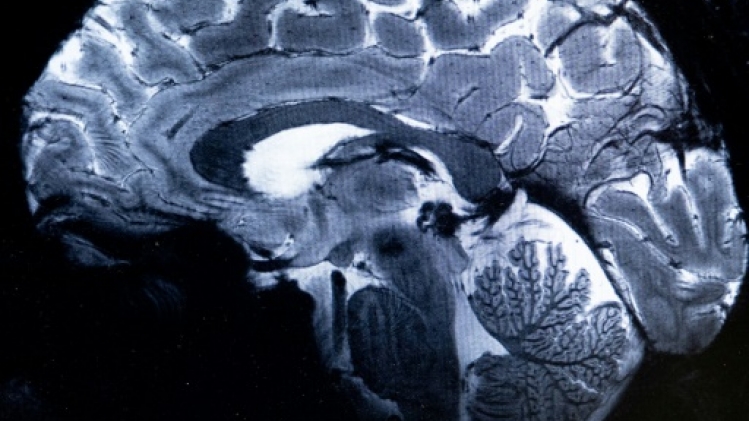

L'IRM le plus puissant du monde a livré, près de Paris, ses premières images du cerveau humain et est désormais prêt à mieux comprendre son fonctionnement et certaines maladies neurodégénératives ou psychiatriques.

Le champ magnétique de cet aimant hors norme atteint 11,7 T (tesla), permettant l'obtention d'images 10 fois plus précises que celles produites actuellement dans les hôpitaux, où la puissance des IRM ne dépasse pas 3 tesla.

Sur l'écran d'Alexandre Vignaud, des images de coupes de cerveau sont comparées avec ce qu'aurait donné un IRM de 3 ou 7 tesla: "Avec cette machine, on peut voir les tout petits vaisseaux qui alimentent le cortex cérébral ou des détails du cervelet qui étaient quasi invisibles jusqu'alors", commente-t-il.